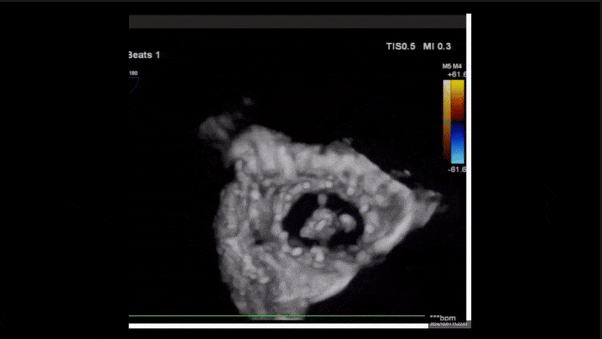

術(shù)后即刻返流三維

術(shù)后三維超聲

術(shù)后即刻經(jīng)食道超聲可見,三尖瓣假體瓣膜位置合適,牛心包瓣葉運動狀態(tài)良好,開閉正常,瓣周及瓣葉對合緣處未見明顯返流,心電圖及心包狀態(tài)較術(shù)前無明顯變化。